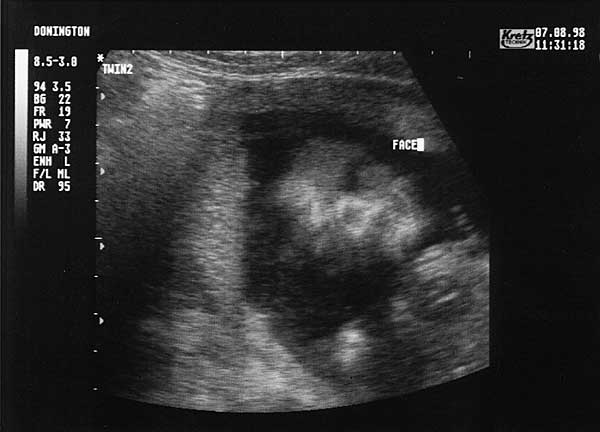

19 Weeks - Friday 7th August 1998

Nineteen Week Scan 3